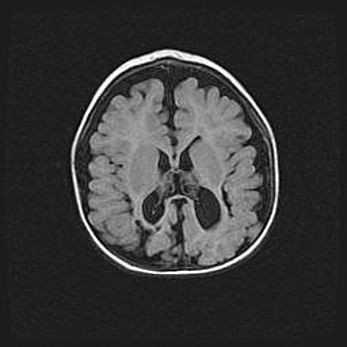

Сообщающаяся гидроцефалия. Кистозная энцефаломаляция головного мозга.

Возраст: 3 месяца 4 дня

Вес: 3100 г

Пол: женский

Окружность головы: 34 см

Срок гестации: 31 неделя

Кистозная энцефаломаляция головного мозга - одна из форм поражения головного мозга в детском возрасте. Характеризуется возникновением множественных и распространённых кист в коре, белом веществе и подкорковых образованиях головного мозга у плодов, новорождённых и детей раннего возраста. Развитие кистозной энцефаломаляции связано с внутриутробной асфиксией и гипотонией, родовой травмой, тромбозом синусов, пороками развития сосудов, инфекциями, сепсисом и другими причинами. Наиболее значимые инфекционные агенты: вирусы простого герпеса, цитомегалии, краснухи, токсоплазмы, энтеробактерии, золотистый стафилококк и другие.